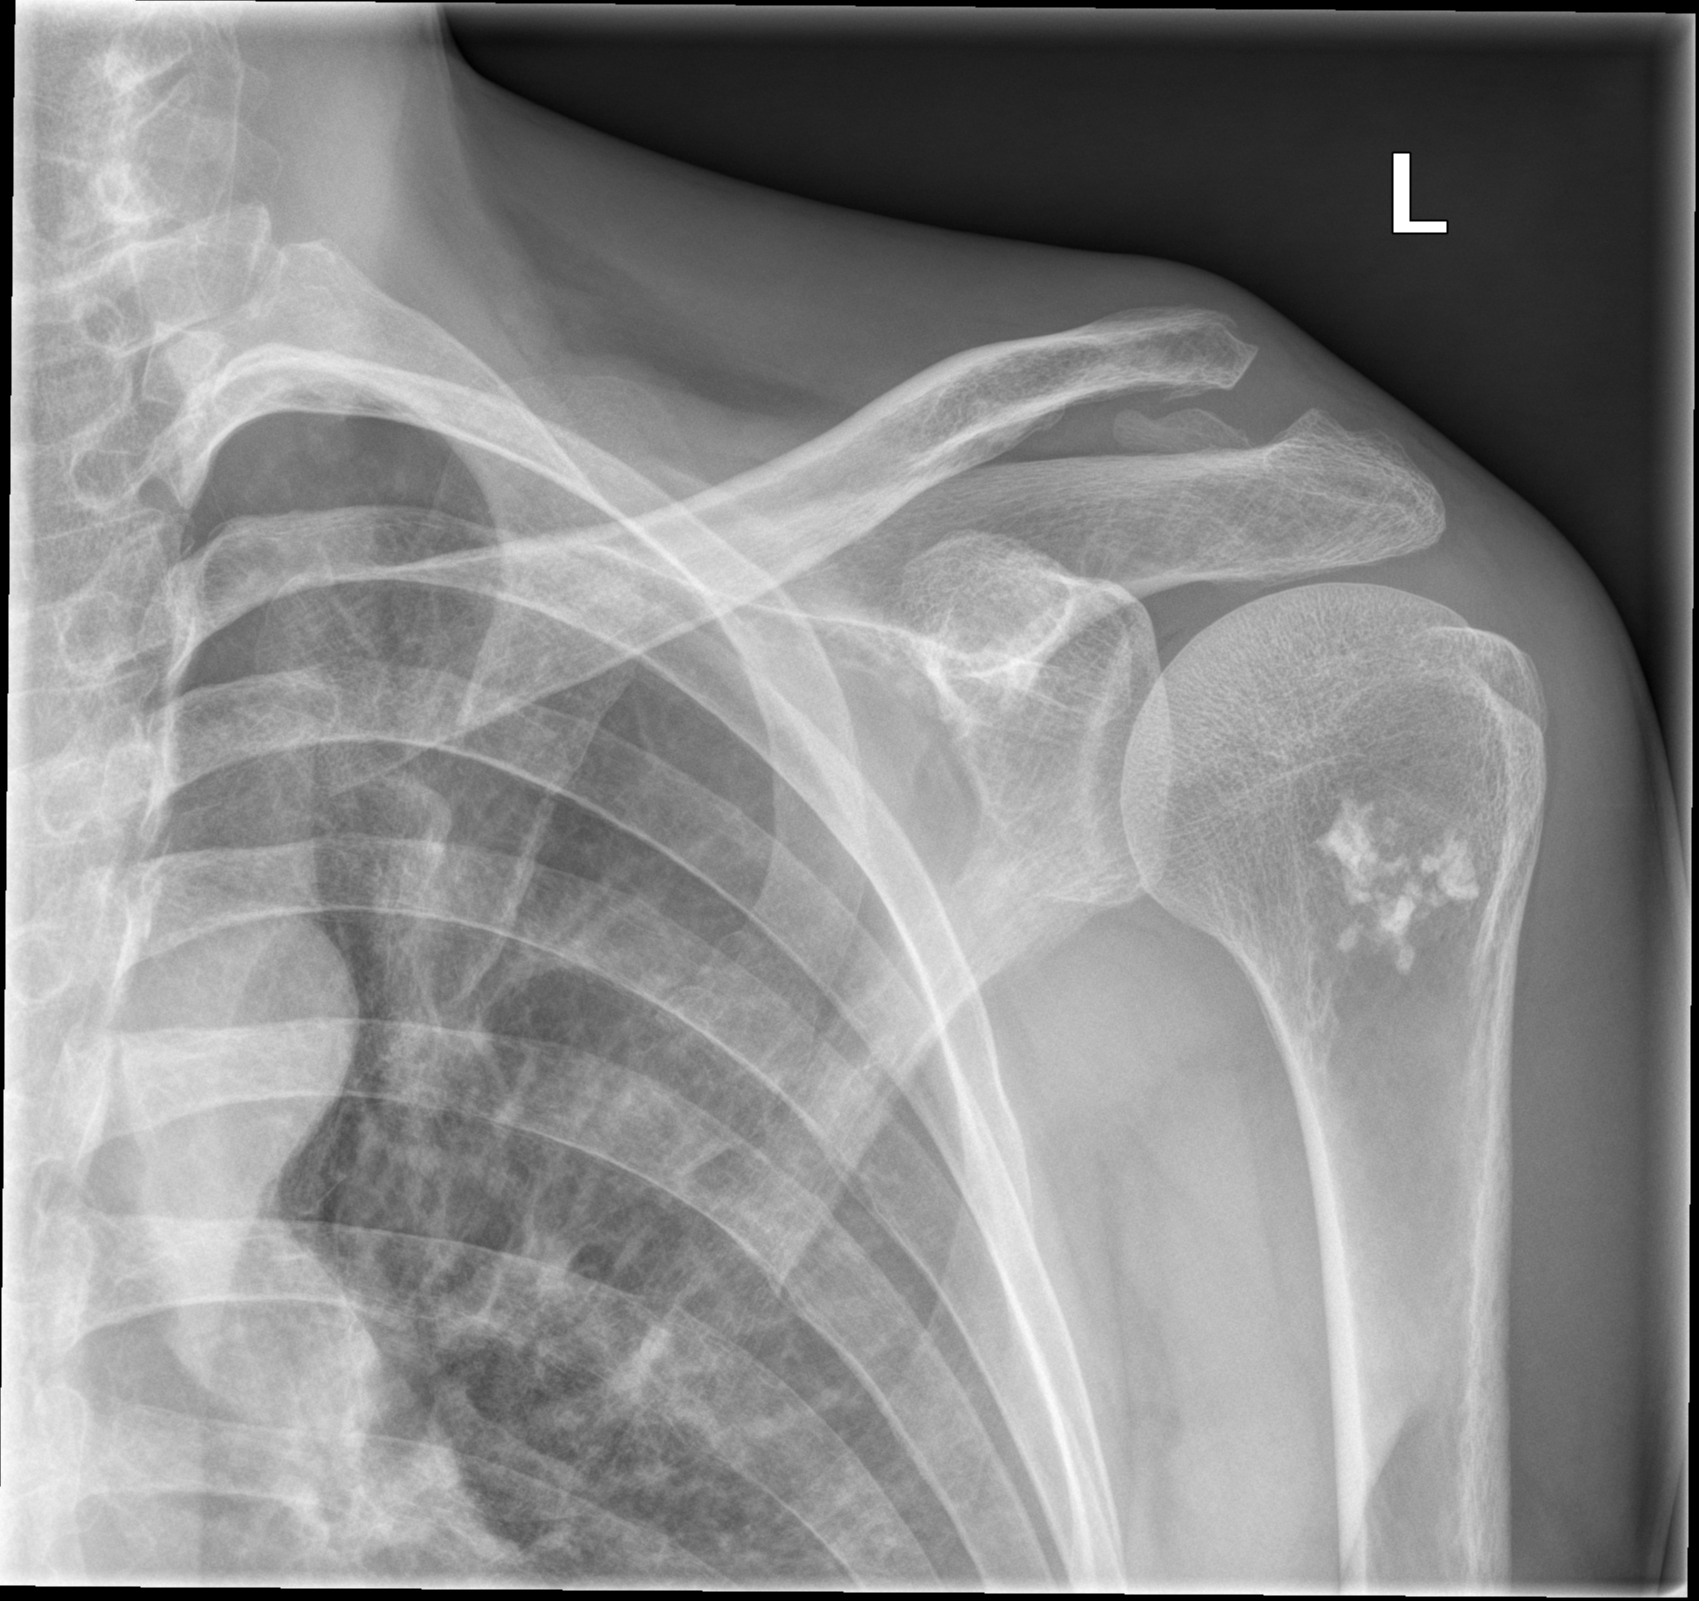

Welches ist die wahrscheinlichste Diagnose für die im vorliegenden Röntgen abgrenzbare Läsion des proximalen Humerus? DDs?